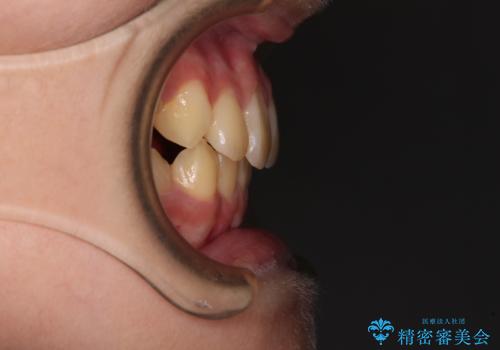

- 前歯の叢生を気にして来院された、小学校3年生女児の患者様です。

身長がやや低く、乳歯から永久歯への交換が少し遅い印象があったので、ワイヤー装置による1期矯正治療ではなく、乳歯も積極的に動かすことのできるインビザライン・ファーストにて治療を行うこととしました。

上顎前歯に過剰歯があったため、まずはその歯を抜歯し、傷が治癒したタイミングでインビザラインを発注することとしました。